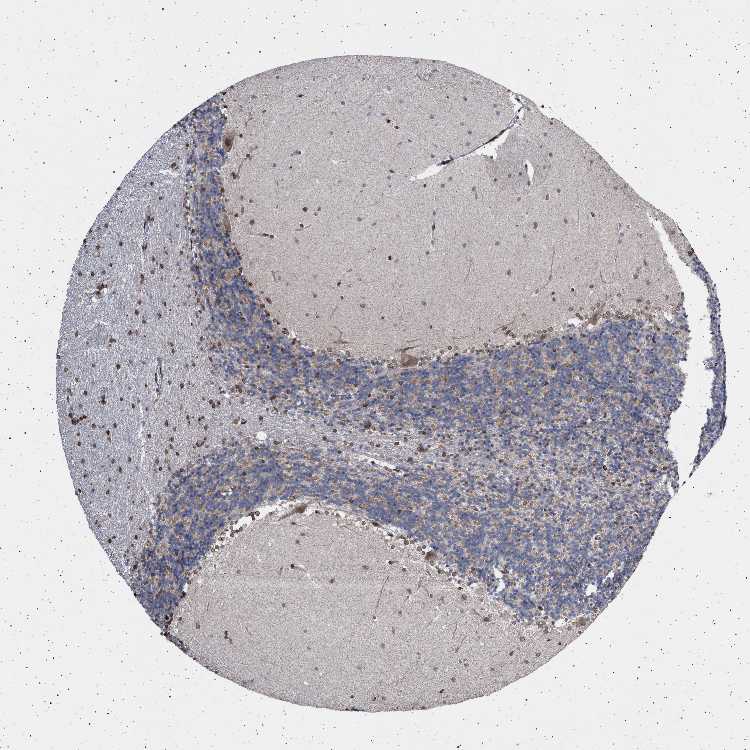

CEREBELLUM - Antibody stainingi

Antibody staining in the annotated cell types in the current human tissue is reported as not detected, low, medium, or high, based on conventional immunohistochemistry profiling in selected tissues. This score is based on the combination of the staining intensity and fraction of stained cells.

Each image is clickable and will lead to virtual microscopy that enables deeper exploration of all samples and also displays staining intensity scores, fraction scores and subcellular localization as well as patient and tissue information for each sample.

Antibody HPA019486Antibody HPA021517

Purkinje cells Not detectedMedium

Cells in granular layer LowLow

Cells in molecular layer HighLow